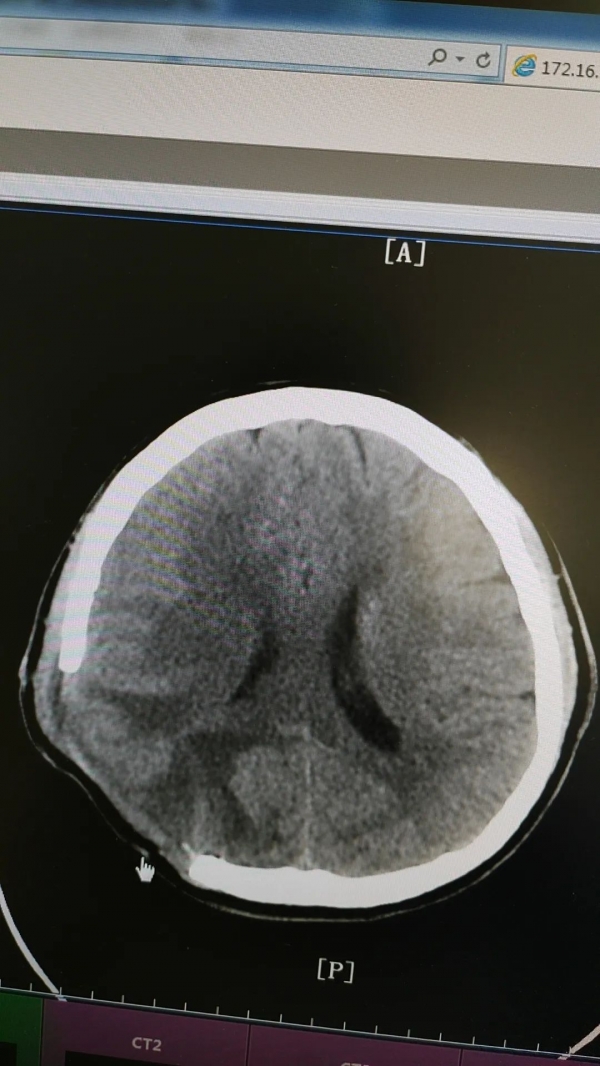

53歲的柴大叔家住湖南長(zhǎng)沙,2023年9月工作需要來(lái)鄭州出差,出差期間突然頭痛、嘔吐起來(lái),隨即撥打120送至我院急診科,經(jīng)過(guò)CT檢查發(fā)現(xiàn),柴大叔右側(cè)頂枕葉腦出血,并有水腫情況,神經(jīng)外科專家張新昌教授立即會(huì)診,柴大叔被確診為“腦出血”并收治外一科治療。

術(shù)前

術(shù)后